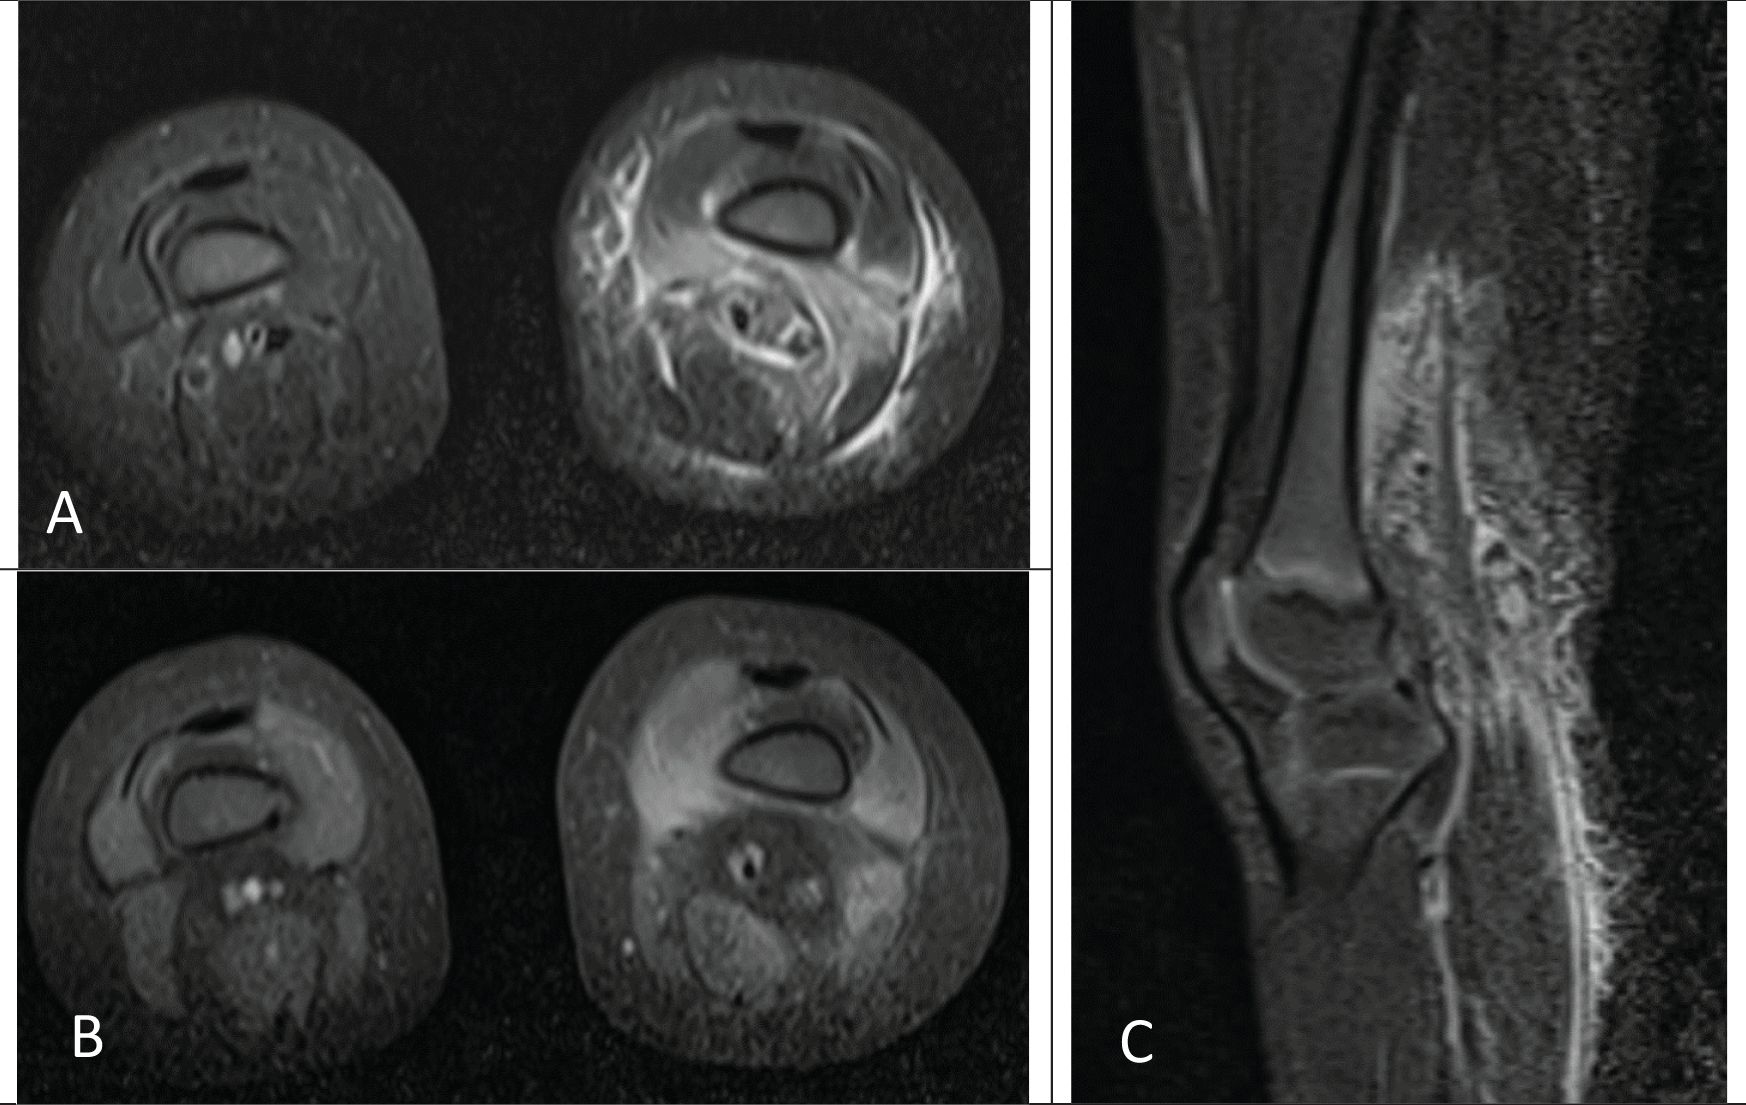

A previously healthy two-year-old Hispanic female was evaluated for left hip and knee pain associated with a fever and a refusal to ambulate. She had been given cephalexin for presumed insect bites on her back and legs. Her past medical history was non-contributory. She was fully immunized. Her family history was negative for consanguinity and inborn errors of immunity. She was afebrile and her physical examination demonstrated a 3 cm circular erythematous lesion on mid left back which was non-indurated. Her left knee was minimally swollen, warm to touch, and non-erythematous. Her hips and knees remained in flexion with demonstrated resistance to knee extension. A nodular 1.5 cm mass in her popliteal fossa was also documented with tenderness upon palpation and she was unable to walk. Her laboratory investigation demonstrated a white blood cell count of 17.2 × 103/uL (normal range: 3.9-13.7), Hgb 10.4 g/dL (normal range:10.2-15.4), platelets 319 × 103 (normal range: 150-450), 64% neutrophils (normal range: 25-72), 26% lymphocytes (normal range: 24-71), 9% monocytes (normal range: 0-14), 0.6% eosinophils (normal range: 2-10), 0.3% basophils (normal range: 0-2), erythrocyte sedimentation rate (ESR) 126 mm/hr (normal range: 0-20), and C-reactive protein (CRP) 68.8 mg/L (normal range: 0-10). A blood culture was negative. Magnetic resonance (MR) imaging of her lower extremity demonstrated myositis and fasciitis involving the soft tissues of the distal left thigh, but no abscess (Figure 1A-C). Likely pathogens included methicillin sensitive Staphylococcus aureus, methicillin resistant Staphylococcus aureus, and group A Streptococcus.

Axial fat-saturated T1-weighted postcontrast MRI of the bilateral lower extremities (B) demonstrates associated enhancement of the vastus medialis, vastus intermedius, and soft tissues of the popliteal fossa. Findings are compatible with myositis with overlying cellulitis.